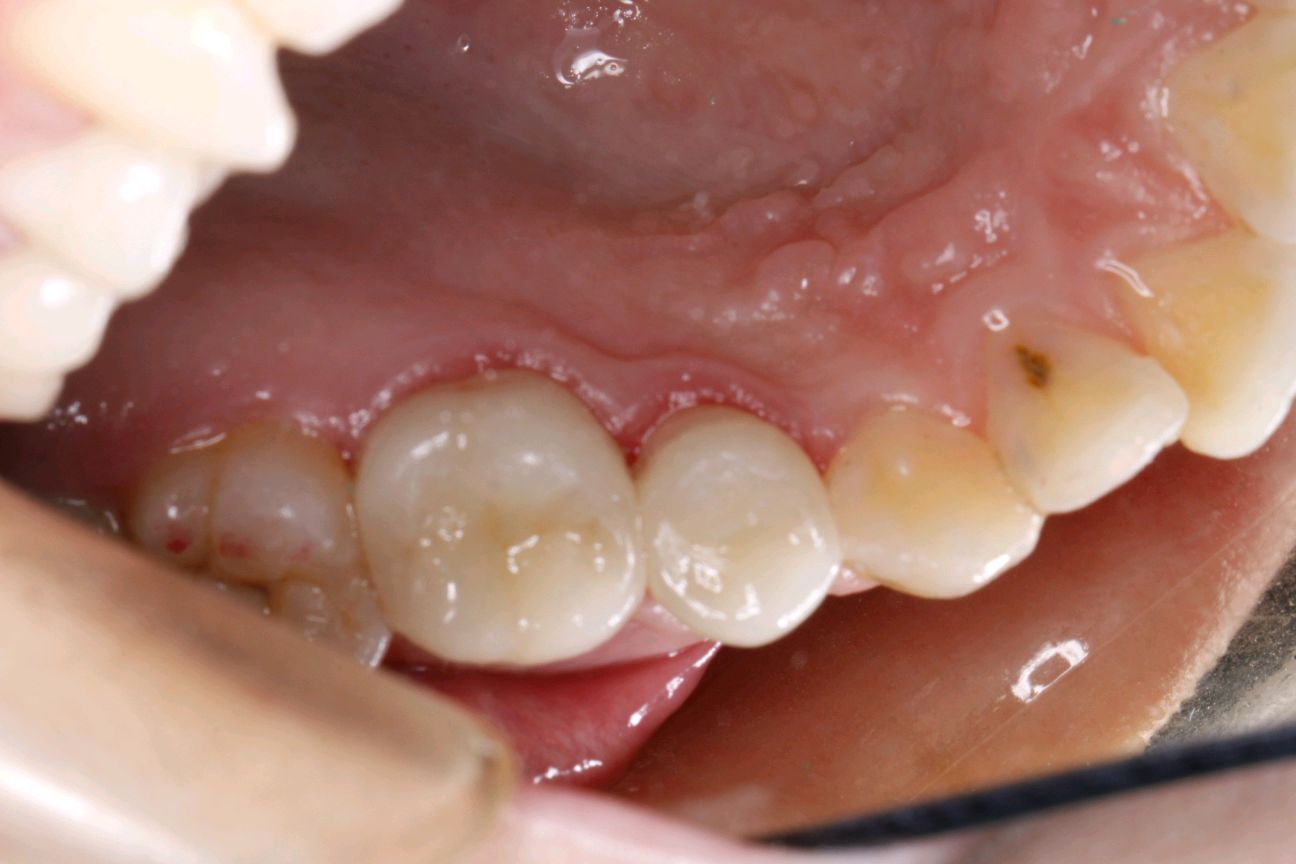

边缘密合性好、咀嚼备感舒适,避免了传统补牙容易脱落、嵌塞食物并造成继发龋等问题;

易清洁邻面可高度抛光,形成良好的邻接关系。光滑的抛光面容易清洁,可以减少菌斑的附着;良好的耐腐蚀性,耐磨性陶瓷可以留存在世间数千年而不腐蚀,故用瓷材料做为嵌体就不存在腐蚀问题;

极佳的生物相容性和美学效果这是全瓷的特性,不存在所谓的金属过敏现象,全瓷的美学效果非常显著;

嵌体是一种少磨牙、能较好恢复咬合关系和邻接关系的有效修复方式;但同时也是一项技术要求较高的修复方式,尤其在牙体预备和粘接流程和细节的把控上难度很大,因此要求医生有较高的专业技术!